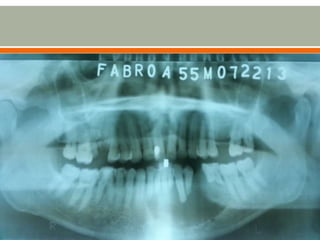

 Patient was immediately brought to OPD wherein

panoramic xray was requested revealing unilocular

radiolucency on the left side of the mandible

2 months PTC Patient was immediately brought to OPD wherein panoramic xray was requested revealing unilocular radiolucency on the left side of the mandible  On follow-up was advised surgery